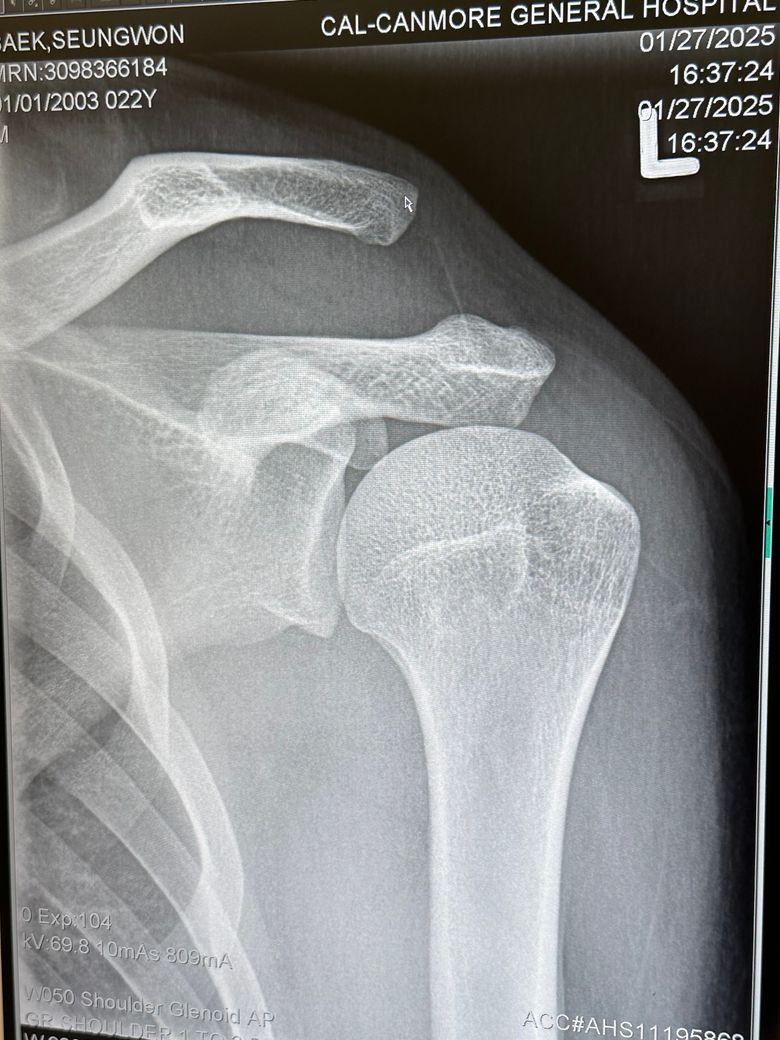

어깨 이거 문제 없이 괜찮은건가요??

캐나다에서 스키타다 심하게 넘어졌습니다 어깨가 안 움직이길래 바로 병원으로 왔고 익스레이도 촬영했습니다 여기 캐나다 병원에서는 문제가 없고 붕대로 감고 있으면 된다고 하면서 설명하기를 나라마다 치료하는 게 다르므로 한국 병원에 다시 가보라고 합니다 아직 여행 일정이 남아 다음주 귀국 예정인데 캐나다 의사선생님 말대로 그냥 붕대만 해도 문제가 없을까요? 캐나다 의사선생님을 믿지 못하는 것이 아니라 한국에서 치료를 받지 못하고 있자니 제 마음이 불안해서 확실하게 알고 싶습니다

• 3번 째 사진

지금 어깨 관절의 뼈 정렬이 좋지 않스니다. 엑스레이 상 보시면 쇄골과 견갑골이 서로 간격이 많이 벌어져있습니다. AC JOINT 라고 해서 쇄골과 견갈골 견봉과의 간격이 너무 벌어져있습니다. 그쪽 인대가 늘어났던지 아니면 삼각근이나 어깨 안정화 시켜주는 근육이 손상을 입은것으로 보입니다. 저런 경우에는 디테일하게 초음파 촬영을 해서 인대에 문제인지 아니면 힘줄에 문제인지를 보고 그에 따른 약물치료나 주사치료를 하면 좋겠지만, 현재 병원에서 하실 수 있는게 고정(붕대)이시면 어깨뼈를 최대한 안정적으로 고정해주시는게 지금 상황에서는 현명한 대처법으로 보입니다. 스키타다가 넘어지면서 AC JOINT라는 관절의 문제가 생긴것으로 보이는데, 일단 인대가 파열이나 끊어진게 아니면 고정 방법으로 해서 연부조직의 자가적인 회복을 기대해볼 수도 있습니다. 우선은 그렇게 해주시는게 좋을거 같습니다.